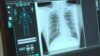

Аналіз даних із України, Таджикистану, Бангладеш, Індії, Індонезії, М'янми, Пакистану, Філіппін, Південної Африки показує, що в середньому на 23 відсотки знизилася кількість випадків діагностики і лікування туберкульозу.

Напередодні Всесвітнього дня боротьби з туберкульозом, який відзначають 24 березня, лікарі попереджають, що прогрес у глобальній боротьбі з цією хворобою був відкинутий пандемією коронавірусу більш ніж на десять років назад. Про це повідомляє кореспондент «Голосу Америки» Генрі Ріджвелл. (Відео: VOA, AFP, Reuters, AP, Skype)